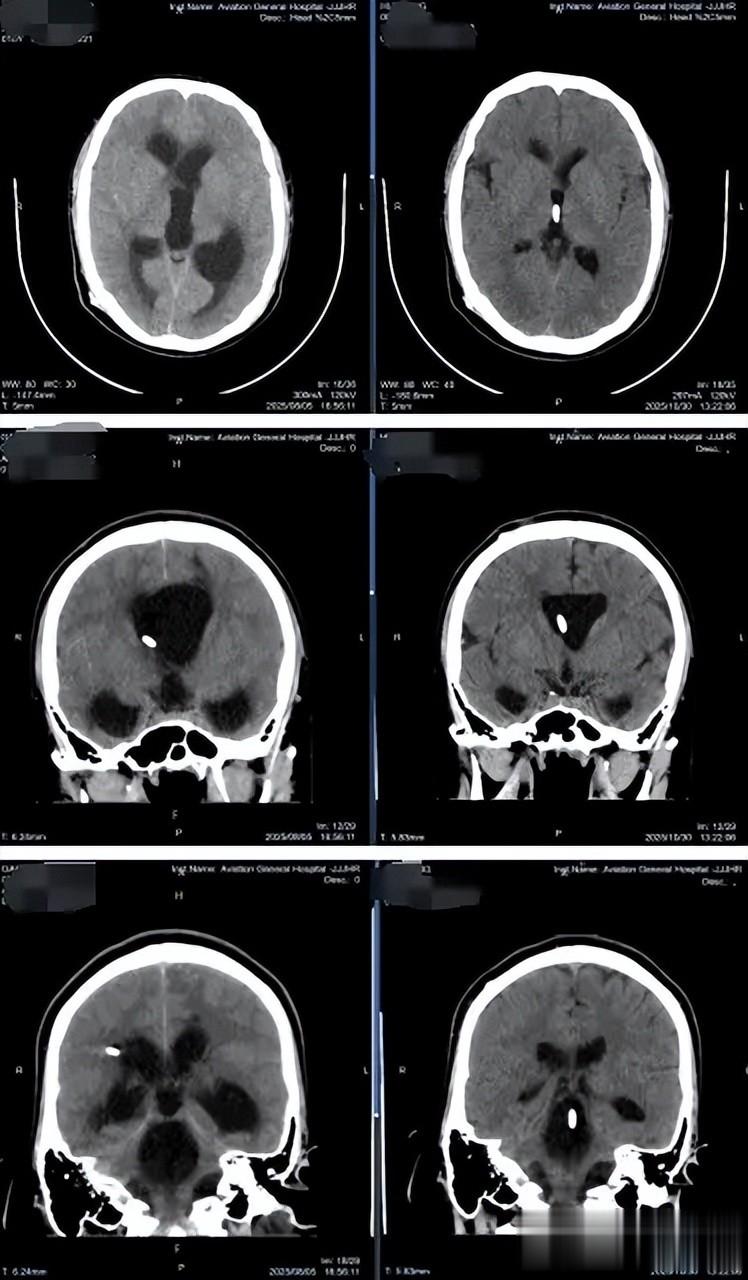

在北京某医院行头颅CT检查后,发现其“脑室系统扩张明显,且第四脑室扩张压迫脑干”。即使静脉用药降颅压,症状也未见改善。到8月5日上午,男孩开始出现“视力下降、视物重影”等危急症状,急性颅内压增高已经压迫视神经。经医生推荐,家人紧急将他送往北京航空总医院,寻求神经外四科肖庆主任的帮助。

影像学检查显示,男孩不仅侧脑室、第三脑室扩张,第四脑室也显著扩张,形成“孤立性第四脑室”样改变。这种情况下,第四脑室内的脑脊液循环受阻,脑干受压,随时可能引发呼吸心跳骤停。且脑脊液检查证实存在“颅内感染”,这很可能是导致分流管失效和脑室粘连的主要原因。

肖庆主任团队为男孩施行了“神经内镜检查术+脑室腹壁长程引流术+分流管去除术”,术中发现脑脊液稍浑浊,脑室壁有污秽灰黑点样增生附着,脑室后角见膜样增生形成——这些都是颅内感染的表现。肖庆主任清除了膜样增生,冲洗了脑室,发现导水管已闭塞。使用3F球囊导管造瘘扩张导水管成型后,内镜得以进入扩张的第四脑室。探查发现第四脑室双侧侧孔、正中孔均闭塞,脑室壁有假包膜膜样增生和增生微血管。最终,在内镜引导下将脑室分流管精准放置,从额部经右侧脑室-右侧室间孔-第三脑室-直达第四脑室。